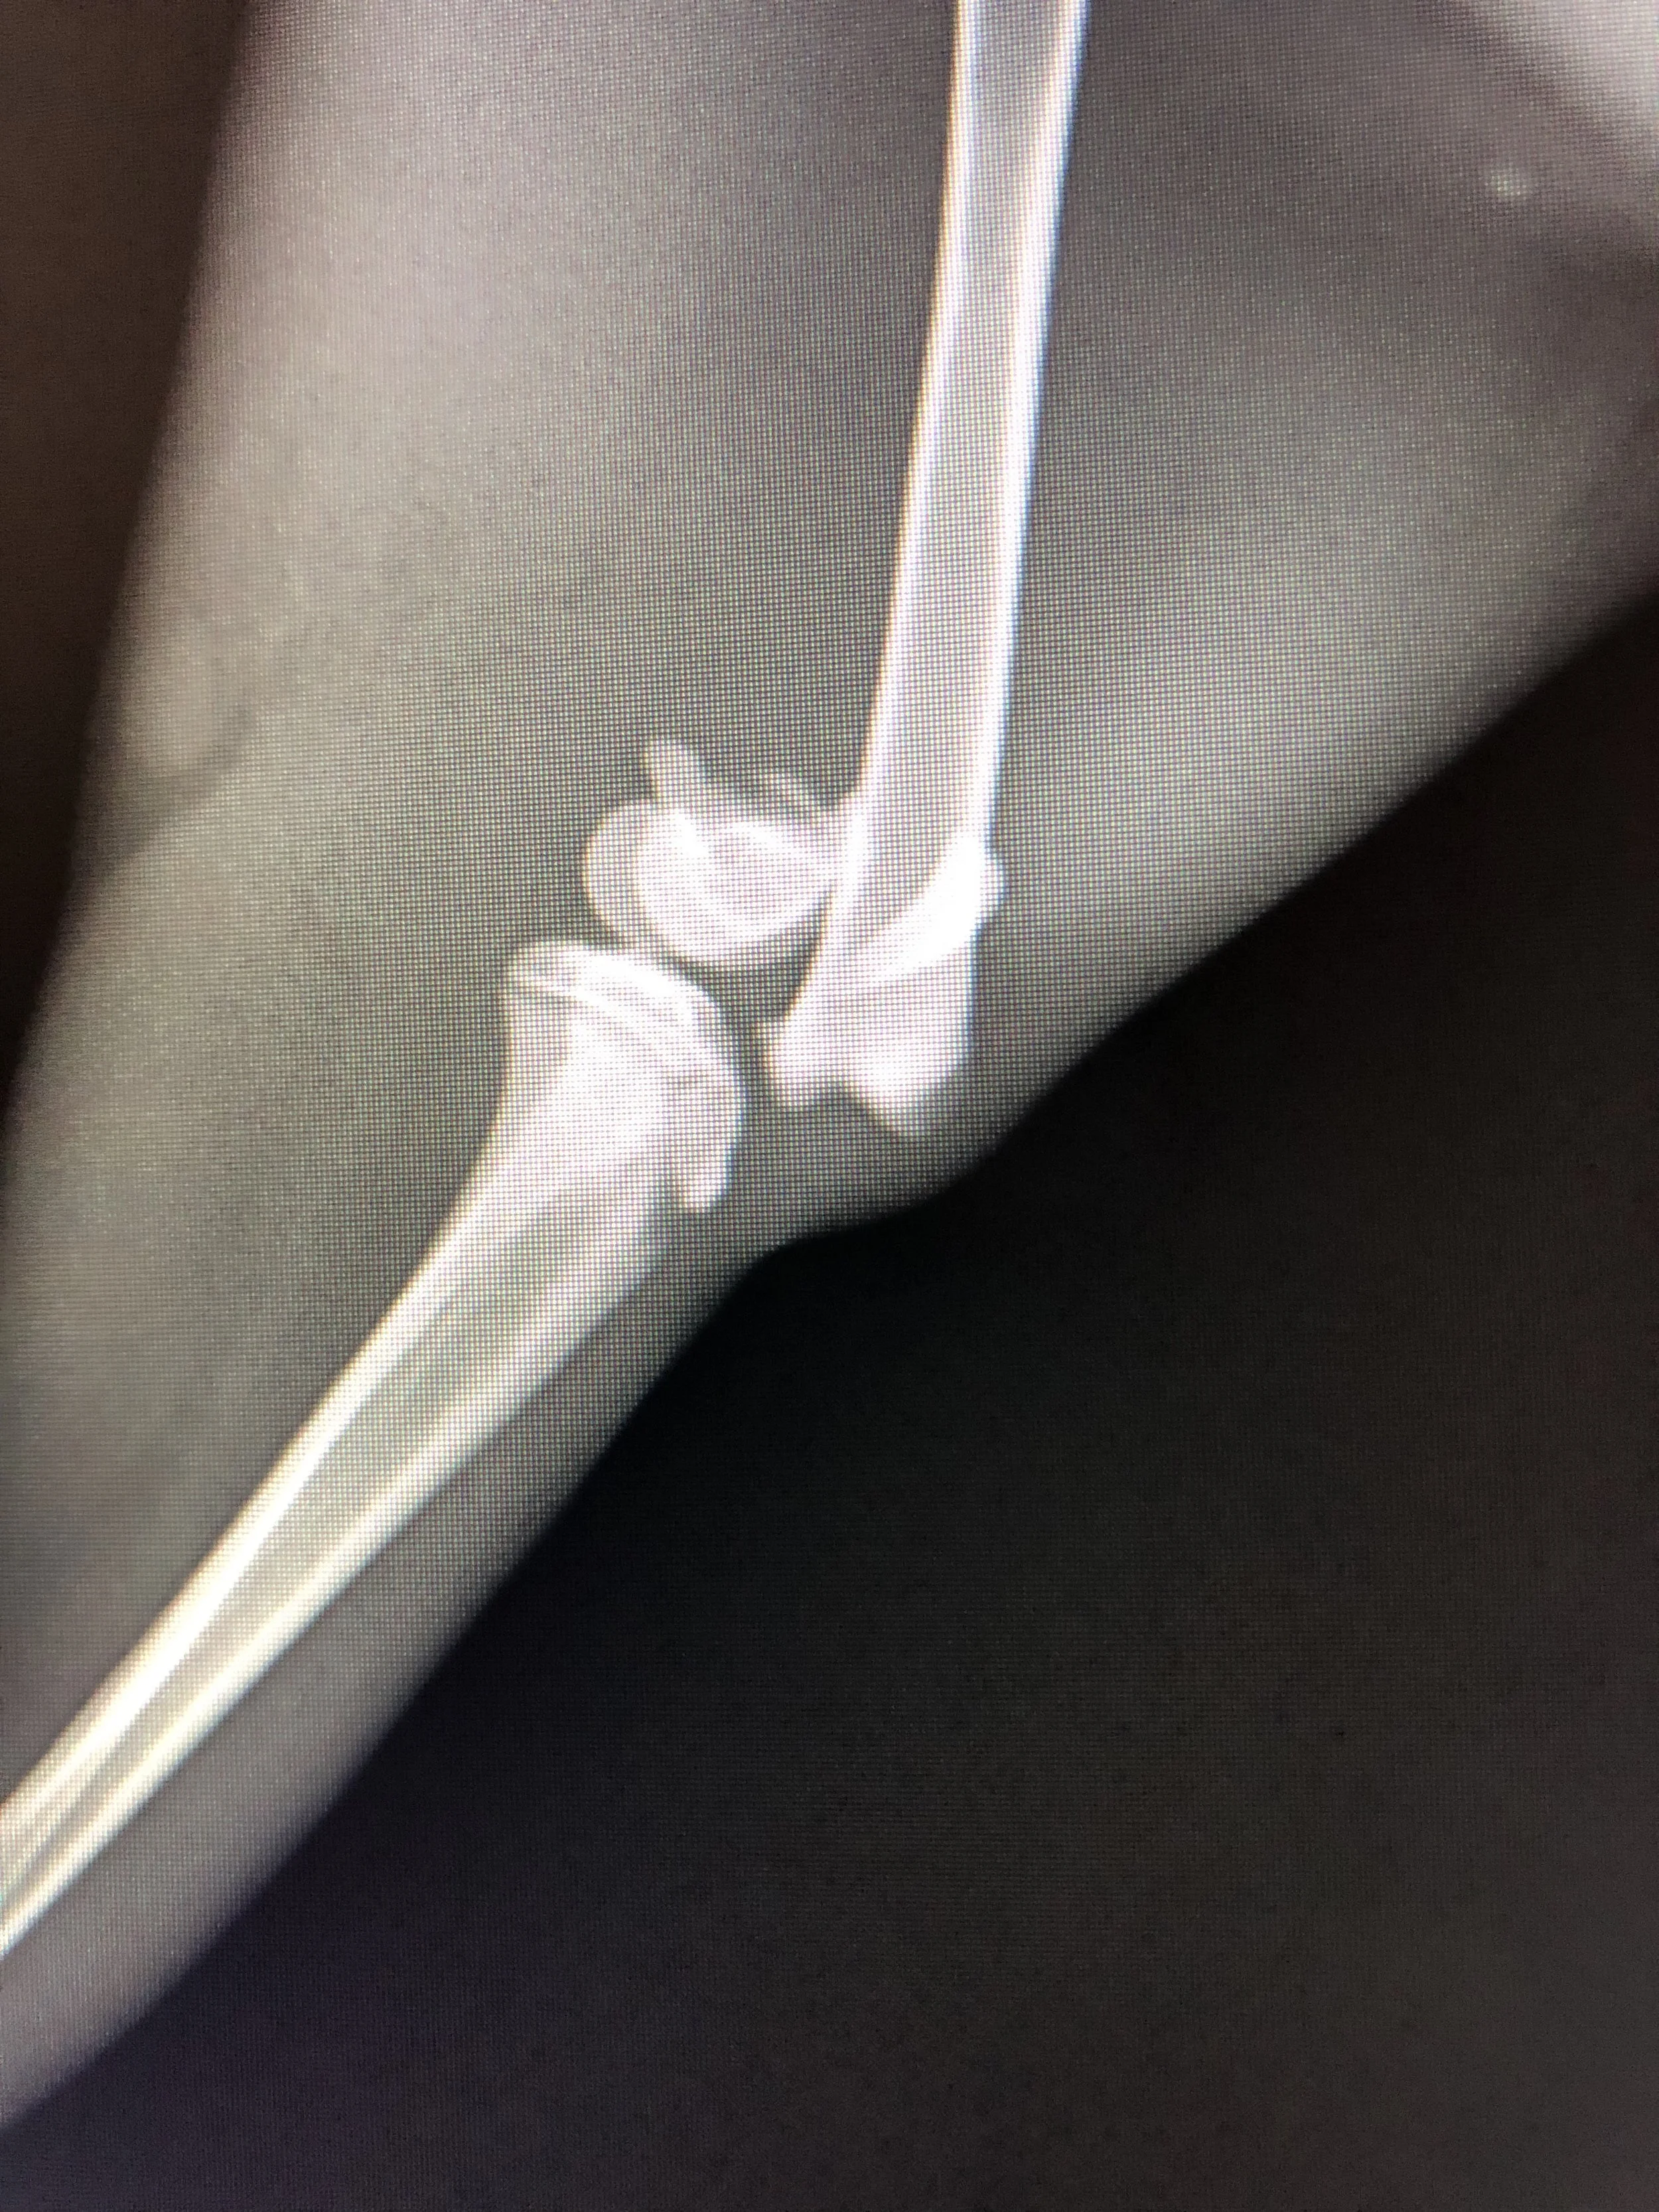

At Silvercreek Animal Hospital, we use digital radiography (X-rays) to help diagnose a wide range of health conditions quickly and safely. X-rays give us a detailed view of your pet’s bones, joints, and internal organs—allowing us to detect issues that can’t be seen during a physical exam alone.

- Broken bones or fractures

- Arthritis and joint problems